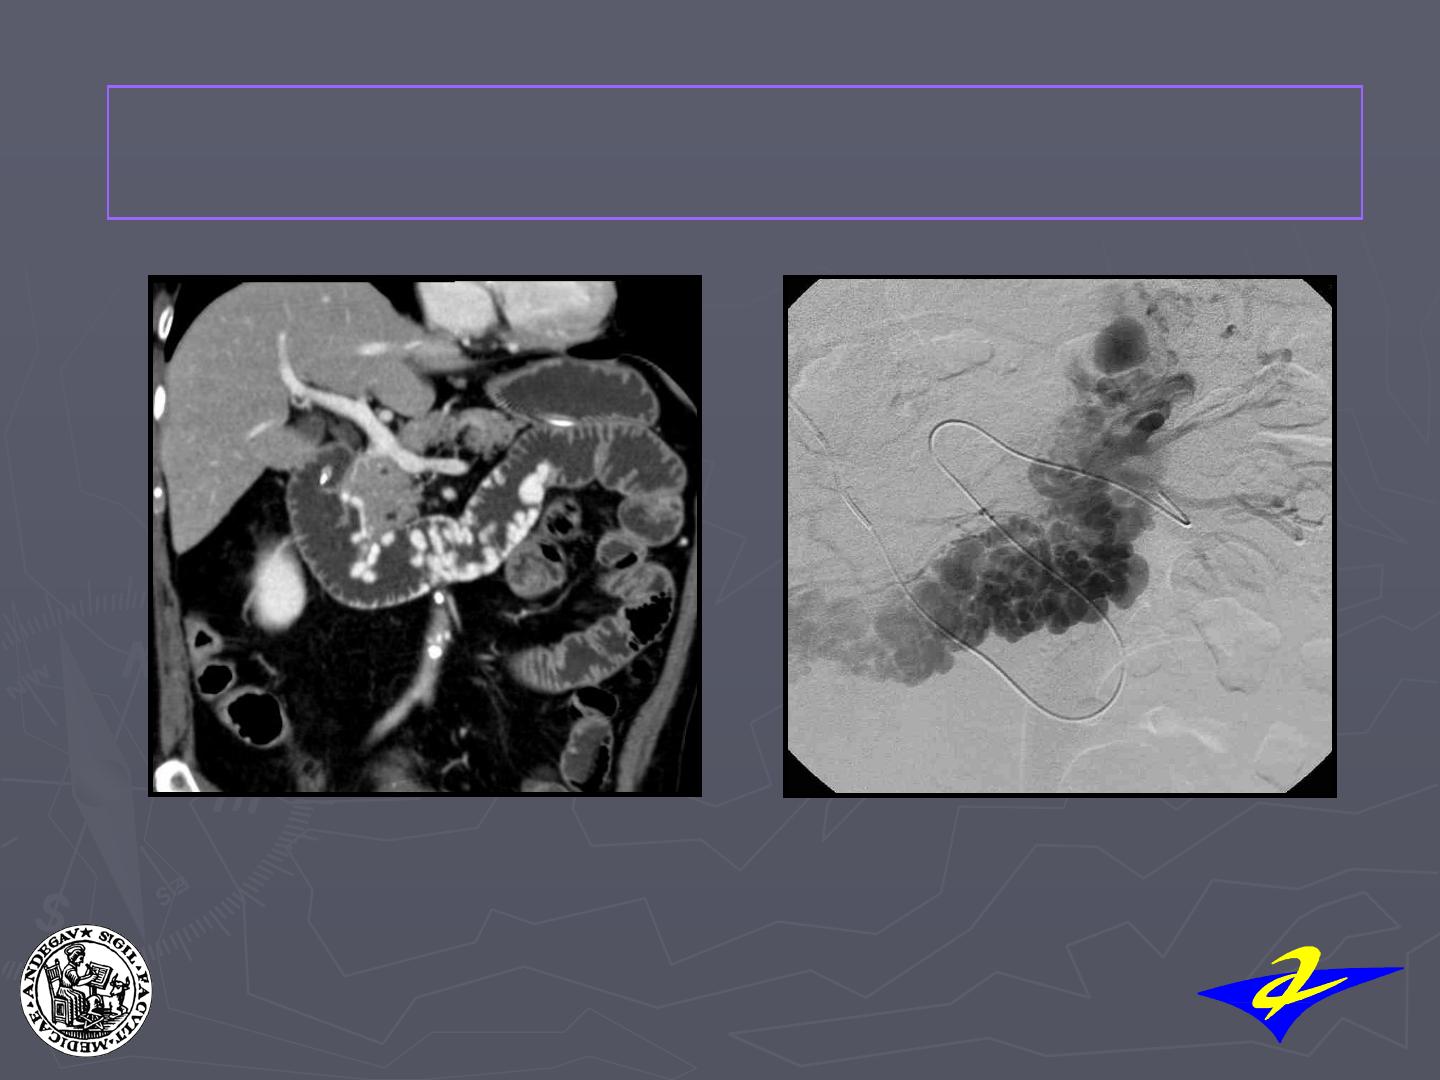

Le diagnostic et le traitement de VD est une urgence VITALE qui repose en

première intention sur l’endoscopie (sclérothérapie/ligature).

En cas d’échec du traitement endoscopique, un traitement endovasculaire

seul ou combiné à un traitement endoscopique peut être indiqué.